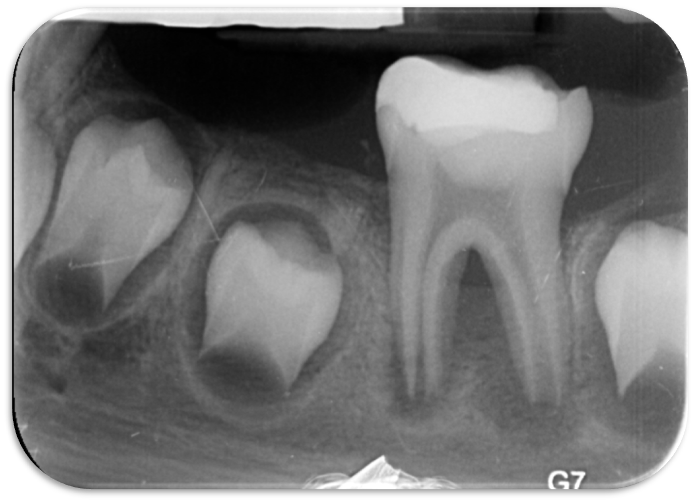

۱. اصول اکسس و یافتن کانال‌های میسینگ

• مولر اول ماگزیلا: کانال MB2 در بیش از ۷۰٪ موارد وجود دارد (Vertucci, 1984). عدم شناسایی آن یکی از شایع‌ترین علل شکست درمان است.

• مولر اول مندیبل: احتمال وجود رادیکس انتومولاریس یا پارامولاریس باید همیشه در نظر گرفته شود.

۲. مدیریت دندان‌های کلسیفیه

• چالش: مسیر کانال به‌وضوح مشخص نیست و ریسک لج یا پرفوریشن وجود دارد.

• استراتژی‌ها:

• CBCT برای تعیین مسیر کانال قبل از شروع

• استفاده از ultrasonic tips زیر میکروسکوپ برای اکسس دقیق

• استفاده از فایل‌های ریز و انعطاف‌پذیر (#6, #8, #10) برای negotiation

• پرهیز از اعمال نیروی زیاد → پیشگیری از ایجاد لج